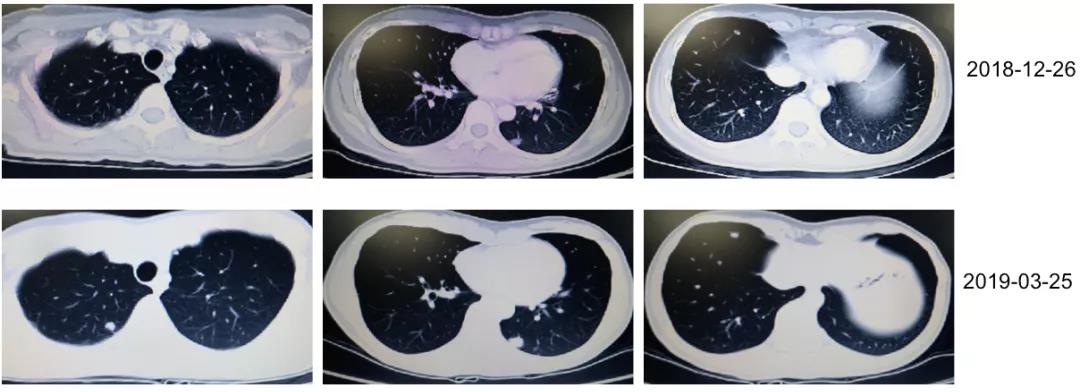

2018年8月17日复查胸腹CT示术区未见占位;腹膜后多发淋巴结肿大,考虑转移。双肺多发结节影,考虑转移瘤可能(图2)。肝S4段结节影,不典型血管瘤,与转移瘤鉴别。CEA 128.6 ng/ml。2018年8月至12月行“贝伐珠单抗+FOLFIRI”方案化疗8周期,具体用药为伊立替康230mg d1,CF 0.5 d1,5-Fu 0.5 iv d1、5-Fu 3.0 CIV46h +贝伐珠单抗200mg d1;q2w。期间复查胸腹CT:双肺多发转移瘤缩小(图3)。CEA持续下降。

3月后疾病再进展,呋喹替尼显疗效